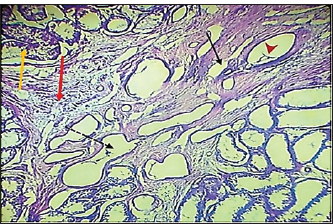

Fig. 7. Histopathological section of testes from a dog in the zinc gluconate group at 30 days post-intrasticular injection, showing exfoliation of germ cells (red arrows), infiltration of inflammatory cells (white arrows), Leydig cell clusters (yellow arrow), edema (star), and congestion (yellow head arrow) (H & E stain 10X). Surgical groupIn the surgical group (GII), the main characteristic findings at 30 days post-surgery were degeneration of seminiferous tubules, multinucleated spermatid, infiltration of inflammatory cells, atrophy of Leydig cells, and vacuole degeneration of basal and Sertoli epithelium (Fig. 8). Furthermore, there was loss of the straight shape of the tubuli recti, disequimentaion of the tubuli recti epithelium, and proliferation of myoid cells (Fig. 9). Other sections showed coagulative necrosis and ghost tubules in the rete testis (Figs. 10 and 11).

Fig. 8. Histopathological section of testes from dogs in the surgical group at 30 days post-surgery, showing degeneration of seminferous tubules (red dotted arrow), multinucleated spermatid (yellow arrows), infiltration of inflammatory cells (red arrow), atrophy of Leydig cells (black arrow), and vacuole degeneration of basel and sertoli epithelium (black dotted arrow) (H & E stain 10X).

Fig. 9. Histopathological section of testes from a dog in the surgical group at 30 days post-surgery, showing loss of the straight shape of the tubuli recti (yellow arrow), disequilibrium of the tubuli recti epithelium (black arrow), proliferation of myoid cells (red arrow), and infiltration of inflammatory cells (red dotted arrow) (H & E stain 40X).

Fig. 10. Histopathological section of testes from a dog in the surgical group at 30 days post-surgery, showing coagulative necrosis (red arrow), ghost tubules in the rete testis (red dotted arrow), and infiltration of inflammatory cells (red head arrow) (H & E stain 10X).

Fig. 11. Histopathological section of testes from a dog in the surgical group at 30 days post-surgery, showing tunica albuginea thickening (white arrows with two heads), inflammatory cell infiltration (yellow arrow), and vacuolar degeneration (red dotted arrow) (hematoxylin and eosin stain 4X). Control groupIn the control group, the histopathological testicular section expresses interstitial septa that surround the seminiferous tubules and contain Leydig cells. Various stages of spermatogenesis and Sertoli cells were also recognized (Fig. 12).